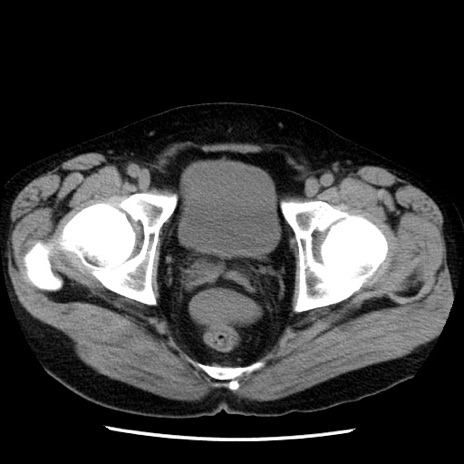

症例29(横断像)

【症例】40歳代男性

【現病歴】2日前から胃痛あり。徐々に周期的な激痛に変化した。本日になっても激痛があるため受診。

【身体所見】意識清明、BT 38-39℃台あり、腹部:膨満、やや硬、右下腹部に圧痛あり。

【データ】WBC 8500、CRP 23.26